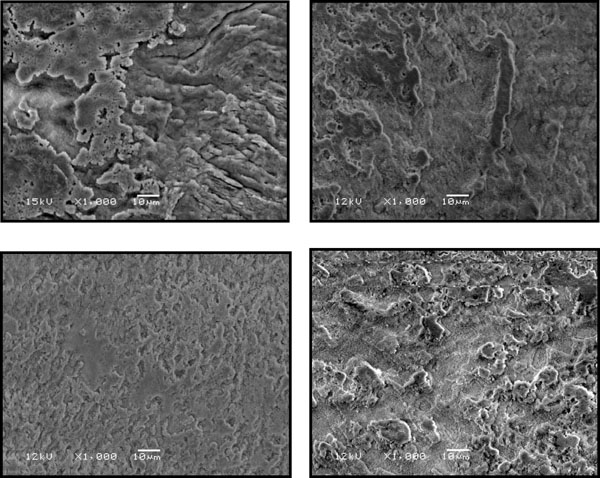

Fig. (3).

The effect of 20 sec etching on enamel of 4 primary molars as observed by SEM at x1000 magnification. Note that the acid affected the aprismatic layer only on all teeth.

Fig. (4).

The effect of 40 sec etching on enamel of 4 primary molars as observed by SEM at x1000 magnification. Note that on 3 teeth the acid affected the aprismatic layer and only on 1 tooth the acid exposed the prismatic layer (lower left).

Fig. (5).

The effect of 60 sec etching on enamel of 4 primary molars as observed by SEM at x1000 magnification. Note that on 3 teeth the acid exposed the prism layer and affected the inter-prismatic layer.

Fig. (6).

The effect of 80 sec etching on enamel of 4 primary molars observed by SEM at x1000 magnification. Note that the acid exposed the prismatic layer on 3 teeth, similar to the effect of 60 seconds etching.

Fig. (2) shows the effect of 20 seconds etching on 2 permanent premolars used as controls. On the left the etching caused removal of interprismatic area (type 1), and on the right the etching caused microporous surface due to removal of the prisms (type 2).

Fig. (3-6) shows the effect of 20, 40, 60 and 80 seconds etching on four primary molar teeth. After 20 seconds the etching solution affected only the aprismatic layer. After 40 seconds the etching solution affected the aprismatic layer on three primary molars and on only one molar the prisms were exposed. After 60 seconds on three primary molars the prisms were exposed and after 80 seconds no significant difference was observed when compared to 60 seconds. Based on these observations an etching time of 60 seconds was used to prepare the enamel for glass-fibers ribbon attachment.